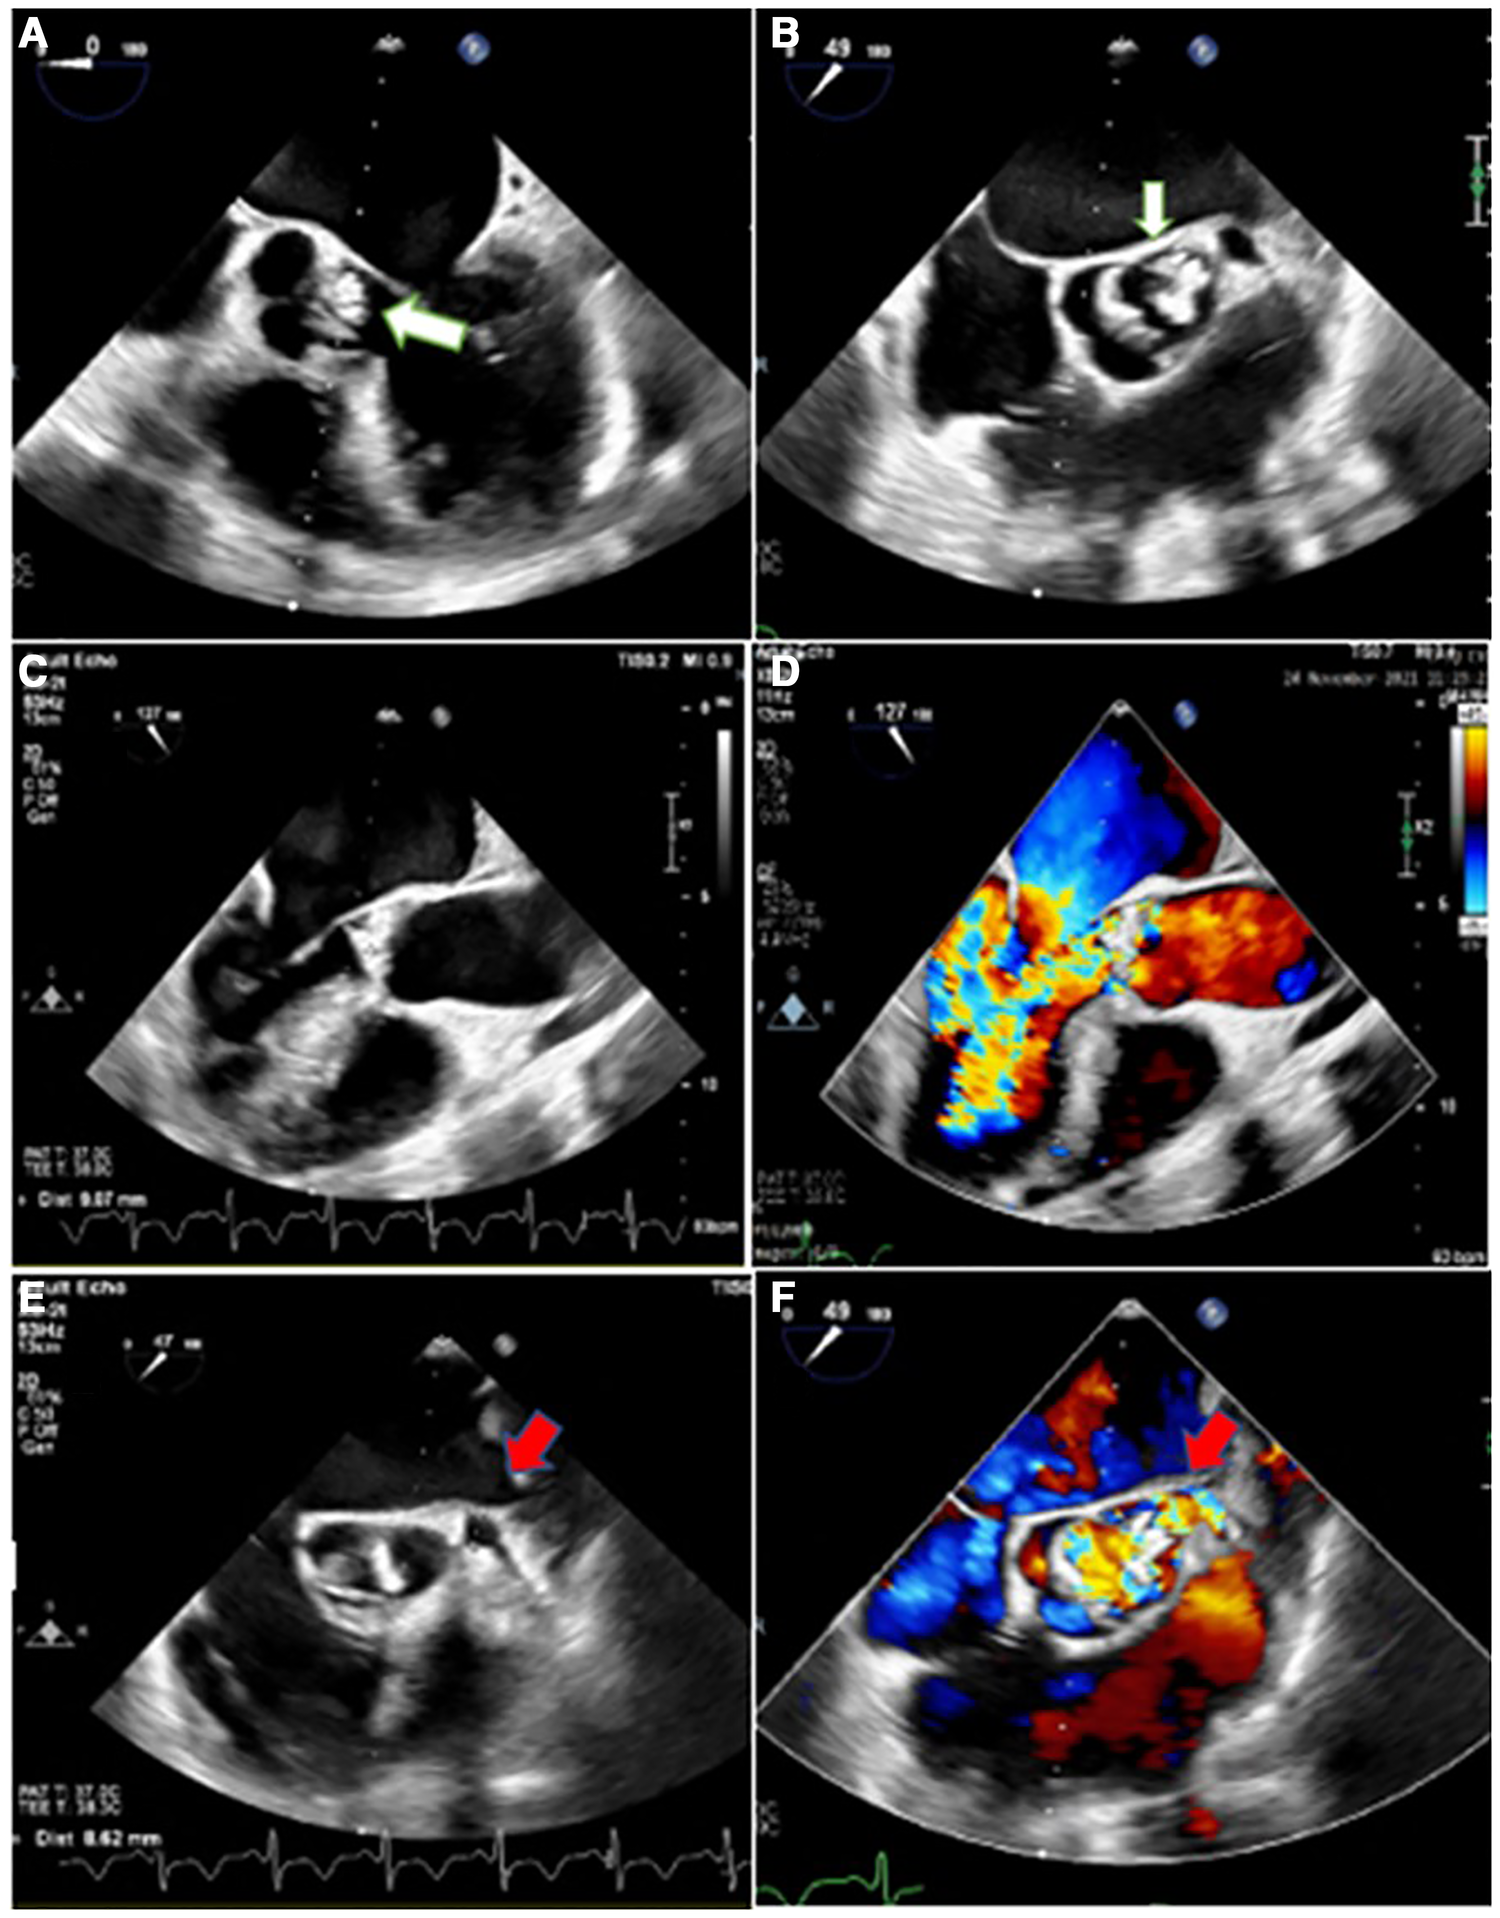

Considering the easily audible systolic and diastolic murmurs on cardiac auscultation, two- and three-dimensional transthoracic and transesophageal echocardiography (2D & 3D TTE and TEE) were performed for better assessment, which revealed an irregularly thickened and destructed bicuspid aortic valve (fusion of non-coronary and right coronary cusps), a few small mobile vegetative lesions, and a partially ruptured left coronary cusp of the aorta, resulting in severe aortic regurgitation (Figure 1). The patient had no aortic ectasia or dilation in view of bicuspid aortic valve or any evidence of endarteritis elsewhere. IE involvement of the mitral valve in the base of the anterior leaflet, adjacent to the aortic valve, with severe mitral regurgitation was also evident (Figure 2). A tricuspid regurgitation with moderate severity and severe pulmonary hypertension (60 mmHg), and severe left ventricular dilatation, accompanied by moderate biventricular systolic dysfunction were also detected. The left main coronary artery was dilated on 2D & 3D TEE.

Figure 1

Two-dimensional transesophageal echocardiography in different views, illustrating irregularly thickened and destructed bicuspid aortic valve (non-coronary cusp and right coronary cusp fusion) with partially ruptured left coronary cusp (white arrow) and a few small mobile vegetative particles, suggestive of aortic valve involvement and destruction by infective endocarditis (A,B), heralding severe aortic insufficiency (C,D). Moreover, it shows the dilated left main coronary artery (red arrow) with turbulent blood flow inside (E,F).